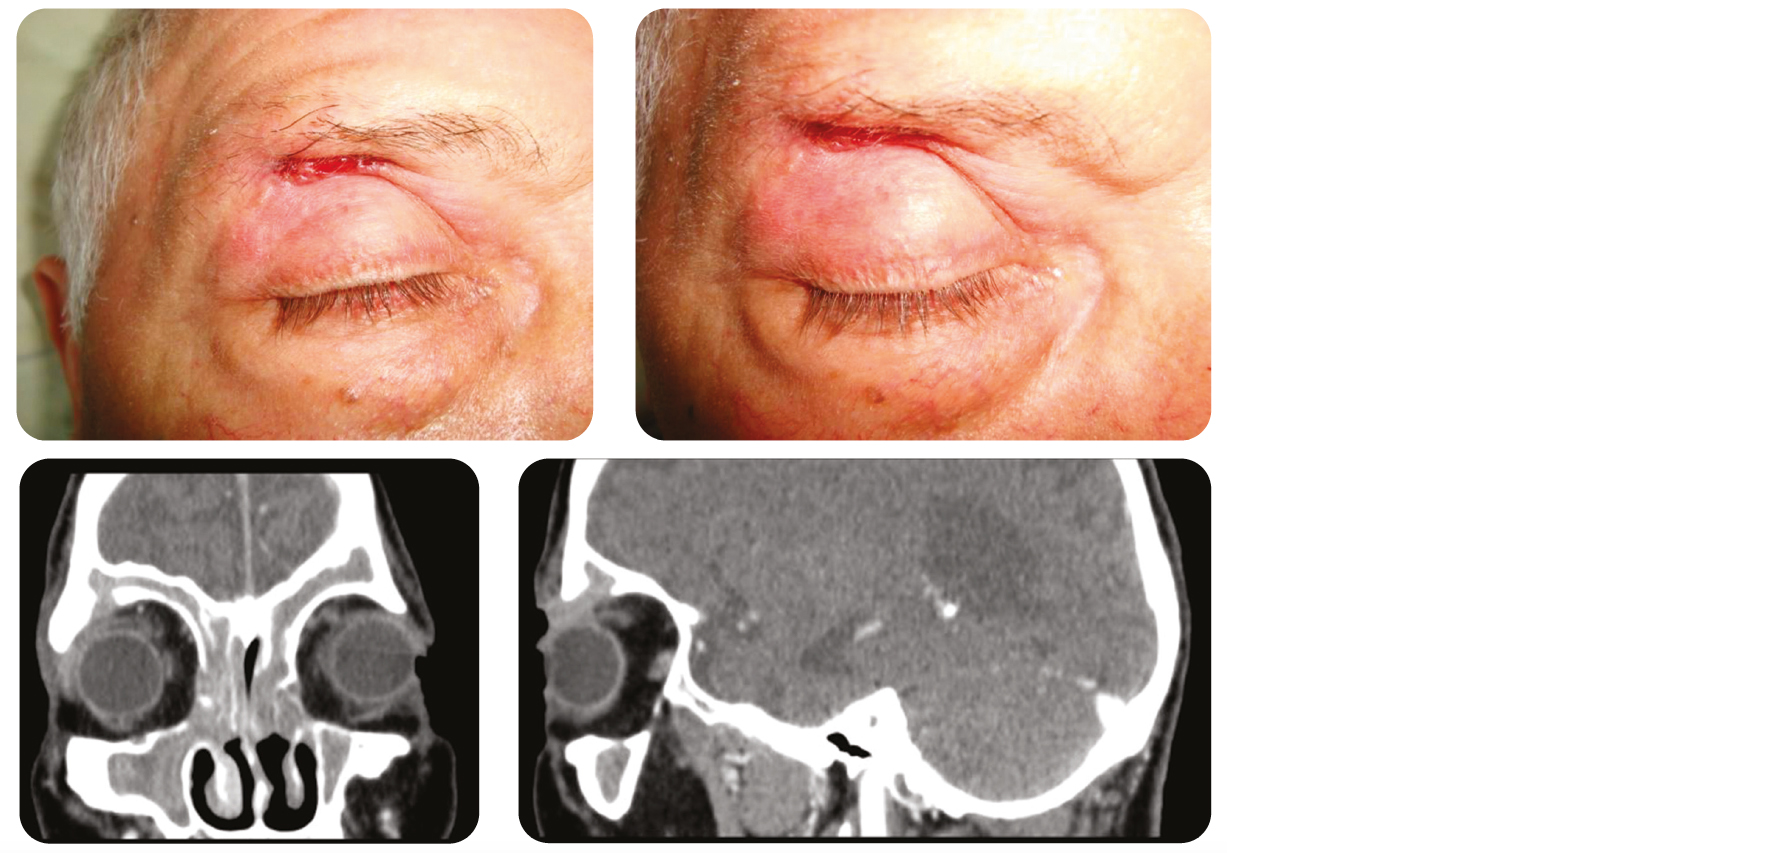

Anamnèse : Homme de 69 ans présentant une lésion de la paupière supérieure droite depuis plus de 6 mois.

Cliniquement : Présence d'une ulcération bourgeonnante de 1.5 cm, adhérente à l'arcade sourcilière, aux bords rétractés.

Mucocèle frontale fistulisée

Tumeur bénigne des sinus causée par une obstruction chronique de l'ostium. Développée le plus souvent au niveau des sinus frontaux et ethmoïdaux, pouvant, rarement, se fistuliser à la peau via l'érosion osseuse provoqué par la pression et l'inflammation locale.

Aspect clinique trompeur pouvant faire évoquer un carcinome.

La présence d'un écoulement et d'une adhérence au plan profond peut orienter vers le diagnostic. Cette lésion se développe de l'intérieur vers l'extérieur, expliquant l'aspect adhérent au plan osseux sous-jacent et les bords rétractés. Le traitement est chirurgical (ORL) et consiste en une décompression endoscopique et un drainage. Une lésion fixée à l'os peut témoigner d'un envahissement de la peau vers la profondeur, ou plus rarement comme dans notre cas de la fistulisation vers la peau d'une lésion sous-jacente. L'examen clef est alors le scanner et non la biopsie cutanée.